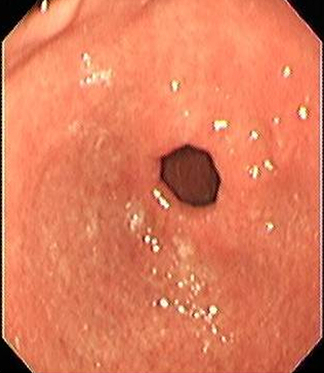

A 30 year old male presented to our clinic with history of on and off epigastric pain of 4 years duration without any alarming symptoms. The patient had no history of offending drug intake. He had been taking proton pump inhibitors Tab. Esomeprazole 20 mg twice daily continuously for 4 years with partial relief. He has been a non smoker and denied any drug abuse or alcohol intake. His systemic examination was unremarkable. He was evaluated on outpatient basis. He had haemoglobin of 14 g/dl with normal leucocytic count and normal platelet count. He had normal liver and kidney function tests. Serum amylase was within normal limits. Abdominal ultrasound showed a normal size of the liver with its normal echo texture. There were no gall stones, the common bile duct was normal and other abdominal viscera were also normal. The patient underwent upper gastrointestinal (GI) endoscopy which revealed a normal esophagus and a small hiatal hernia. There were multiple polyps in the antral area, each around 1 cm (Figure 1 [Fig. 1]). A biopsy was taken from these polyps and a Campylobacter-like organism (CLO) test was also done. The patient's biopsy (Figure 2 [Fig. 2]) revealed evidence of chronic gastritis with no H. pylori activity. The polyp was adenomatous with no features of malignancy. His serology for H. pylori was negative. The patient had a normal colonscopic examination and familial polyposis was ruled out.

Figure 1: Endoscopy showing multiple polyps in the antral area of the stomach